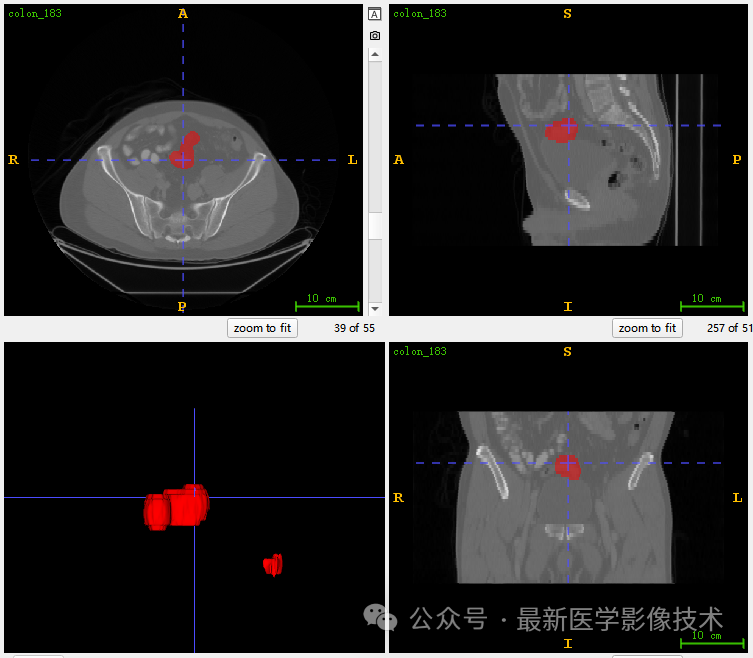

5、验证集分割结果

左图是金标准结果,右图是预测结果。